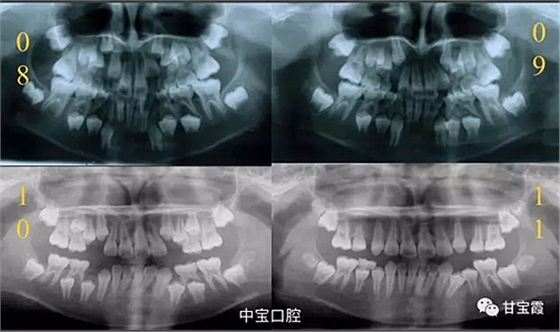

有一個七歲的小女孩,在替牙時媽媽發(fā)現(xiàn)孩子新長的牙不整齊,有一顆長到里面了,上下頜中線也不對稱,很著急就來到門診看牙。

經(jīng)過我臨床檢查和X線的診斷,決定早期干預(yù),每三個月定期復(fù)診檢查一次,并拔掉了幾個乳牙和四個恒牙,正畸專業(yè)叫序列拔牙。

經(jīng)過三年零九個月的看護(hù),最終戴上了固定矯治器,但是大家不難發(fā)現(xiàn),孩子的牙齒已經(jīng)排齊,上下中線也基本對齊,面型也好看多了,這樣矯正就變得簡單,療程自然縮短,孩子也不遭罪了。

這個故事告訴我們,只有家長早點把孩子帶給正畸醫(yī)生檢查,才能早期發(fā)現(xiàn)早期治療。起到了事半功倍的效果。矯正以后還不容易復(fù)發(fā),因為從08年的初診到11年戴矯正器這三年多的時間里,孩子的牙齒是自己長好的。